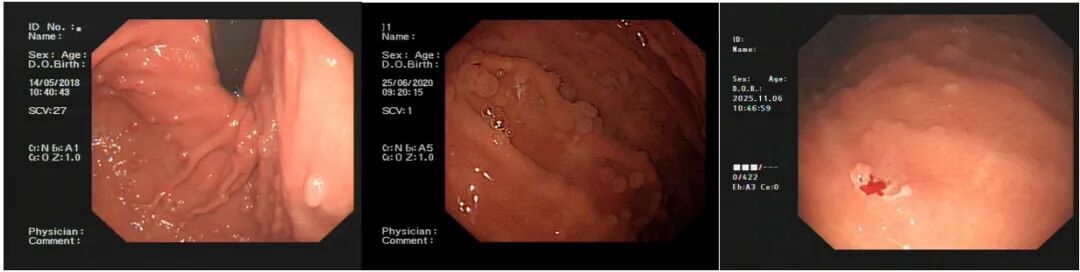

病史摘要:患者为 49 岁女性,因“反复胃肠道息肉切除 17 年余,腹胀 3 天”入院。既往有多部位囊肿,曾行右侧颈部神经鞘瘤手术。家族中父亲、两个哥哥均有结肠息肉相关病史。2008 年首次发现胃底、胃体、结肠等多发性息肉,病理为胃底腺瘤性息肉,此后多次行胃肠镜检查及内镜下息肉切除术。 诊疗过程:入院查体生命体征平稳,慢性病容,上腹轻压痛。2019 年基因检测提示 A